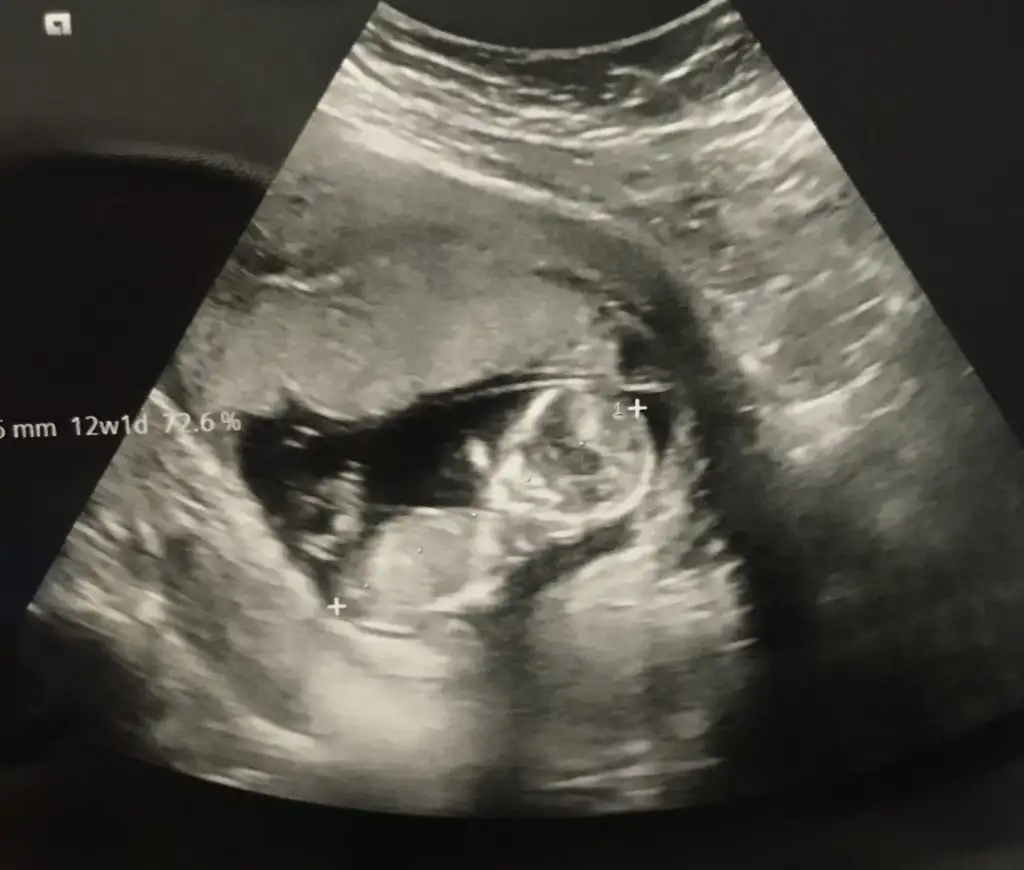

banada tahmin yapabilir misiniz 12haftalik![]()

Bence kız gibi

Bence senin bebiş kız canım bende az cok anlıyorum tahminlerim de cogu zaman tutuyor

Erkek gibi sanki eninde olamadim çok karanlık nubu sanki biraz bir diklik var umarım u nubturIkra meyra 12+1 iz bize de tahmin de bulunabilir misiniz![]()